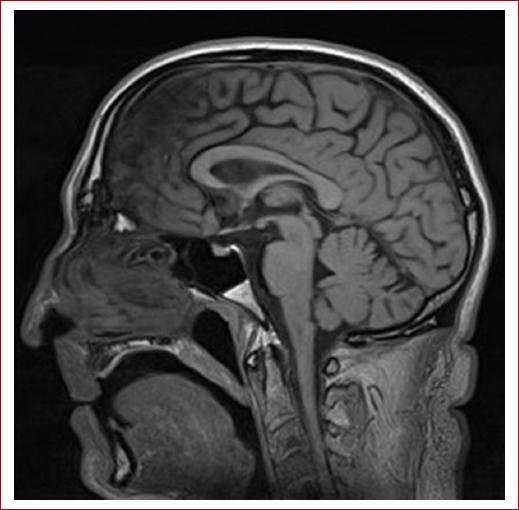

Se realiza una ecografía de troncos supraaórticos (TSA), en la cual se objetivan pequeñas placas de ateroma en ambos bulbos carotídeos. En el eje carotídeo derecho se evidencia un flujo atenuado con ascenso sistólico lento y velocidad pico sistólica disminuida. La arteria vertebral derecha muestra una velocidad pico sistólica elevada, con ausencia de flujo diastólico y morfología de inversión de flujo en diástole en relación con la actividad del miembro superior derecho. Se realiza una angiotomografía de TSA que muestra ateromatosis calcificada en segmentos petrosos de ambas arterias carótidas internas (Fig. 1) y estenosis de aproximadamente 8 mm de longitud del origen del TBC con una reducción de diámetro superior al 90%, y con dilatación posestenótica, como puede observarse en la reconstrucción 3D de las imágenes tomográficas (Fig. 2). En la resonancia magnética cerebral se aprecian lesiones sugestivas de eventos isquémicos previos en el lóbulo frontal derecho distal correspondientes a territorios de la arteria cerebral anterior y la arteria cerebral media derecha (Fig. 3), por lo que se ingresa al paciente en la unidad de ictus.

Figura 3 Eje carotídeo derecho: se evidencia un flujo atenuado con ascenso sistólico lento y velocidad pico sistólica disminuida.